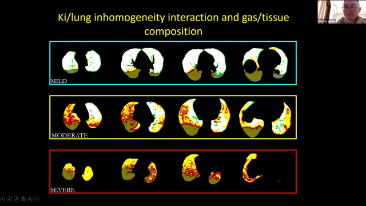

La elecciĂłn de la configuraciĂłn correcta del respirador para el tratamiento de pacientes con enfermedades de las vĂas respiratorias es un asunto muy importante. Dado que un mĂ©dico es responsable de la tarea de especificar los parĂĄmetros del equipo de ventilaciĂłn en su totalidad, el conocimiento y la experiencia del mĂ©dico en la selecciĂłn de estos ajustes tiene un efecto directo en la precisiĂłn de sus decisiones. El paradigma de la atenciĂłn de apoyo de los pacientes ha cambiado significativamente durante los Ășltimos 20?a?os. Hoy en dĂa, se han desarrollado varios modos de ventilaciĂłn y herramientas de apoyo de la toma de decisiones en torno a las necesidades clĂnicas para ayudar a los profesionales a mejorar la eficiencia y eliminar errores en estas decisiones.

Al integrar la oxigenoterapia de alto flujo, la ventilaciĂłn no invasiva y la ventilaciĂłn invasiva, los respiradores 3?en?1 de la serie?SV combinan un desempe?o estable, funciones versĂĄtiles y facilidad de uso. Las excepcionales caracterĂsticas de protecciĂłn pulmonar y las numerosas herramientas de apoyo de la toma de decisiones se dise?aron para reducir el riesgo de infecciĂłn cruzada y facilitar el trabajo diario de los profesionales.